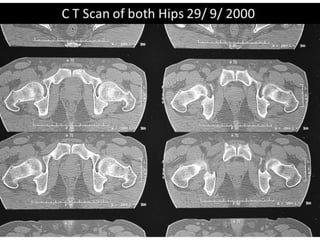

The document presents a detailed case study of a patient with transient osteoporosis of the hip (TOH) and spontaneous osteonecrosis of the knee (SONK) treated at Choithram Hospital & Research Centre in India. Over 20 years, the patient experienced multiple episodes of TOH and SONK with no history of trauma or co-morbidities, resulting in resolutions and recurrences of conditions. The information is intended for orthopedic surgery students and highlights personal experiences and case collections, with a disclaimer regarding content usage and potential controversies.